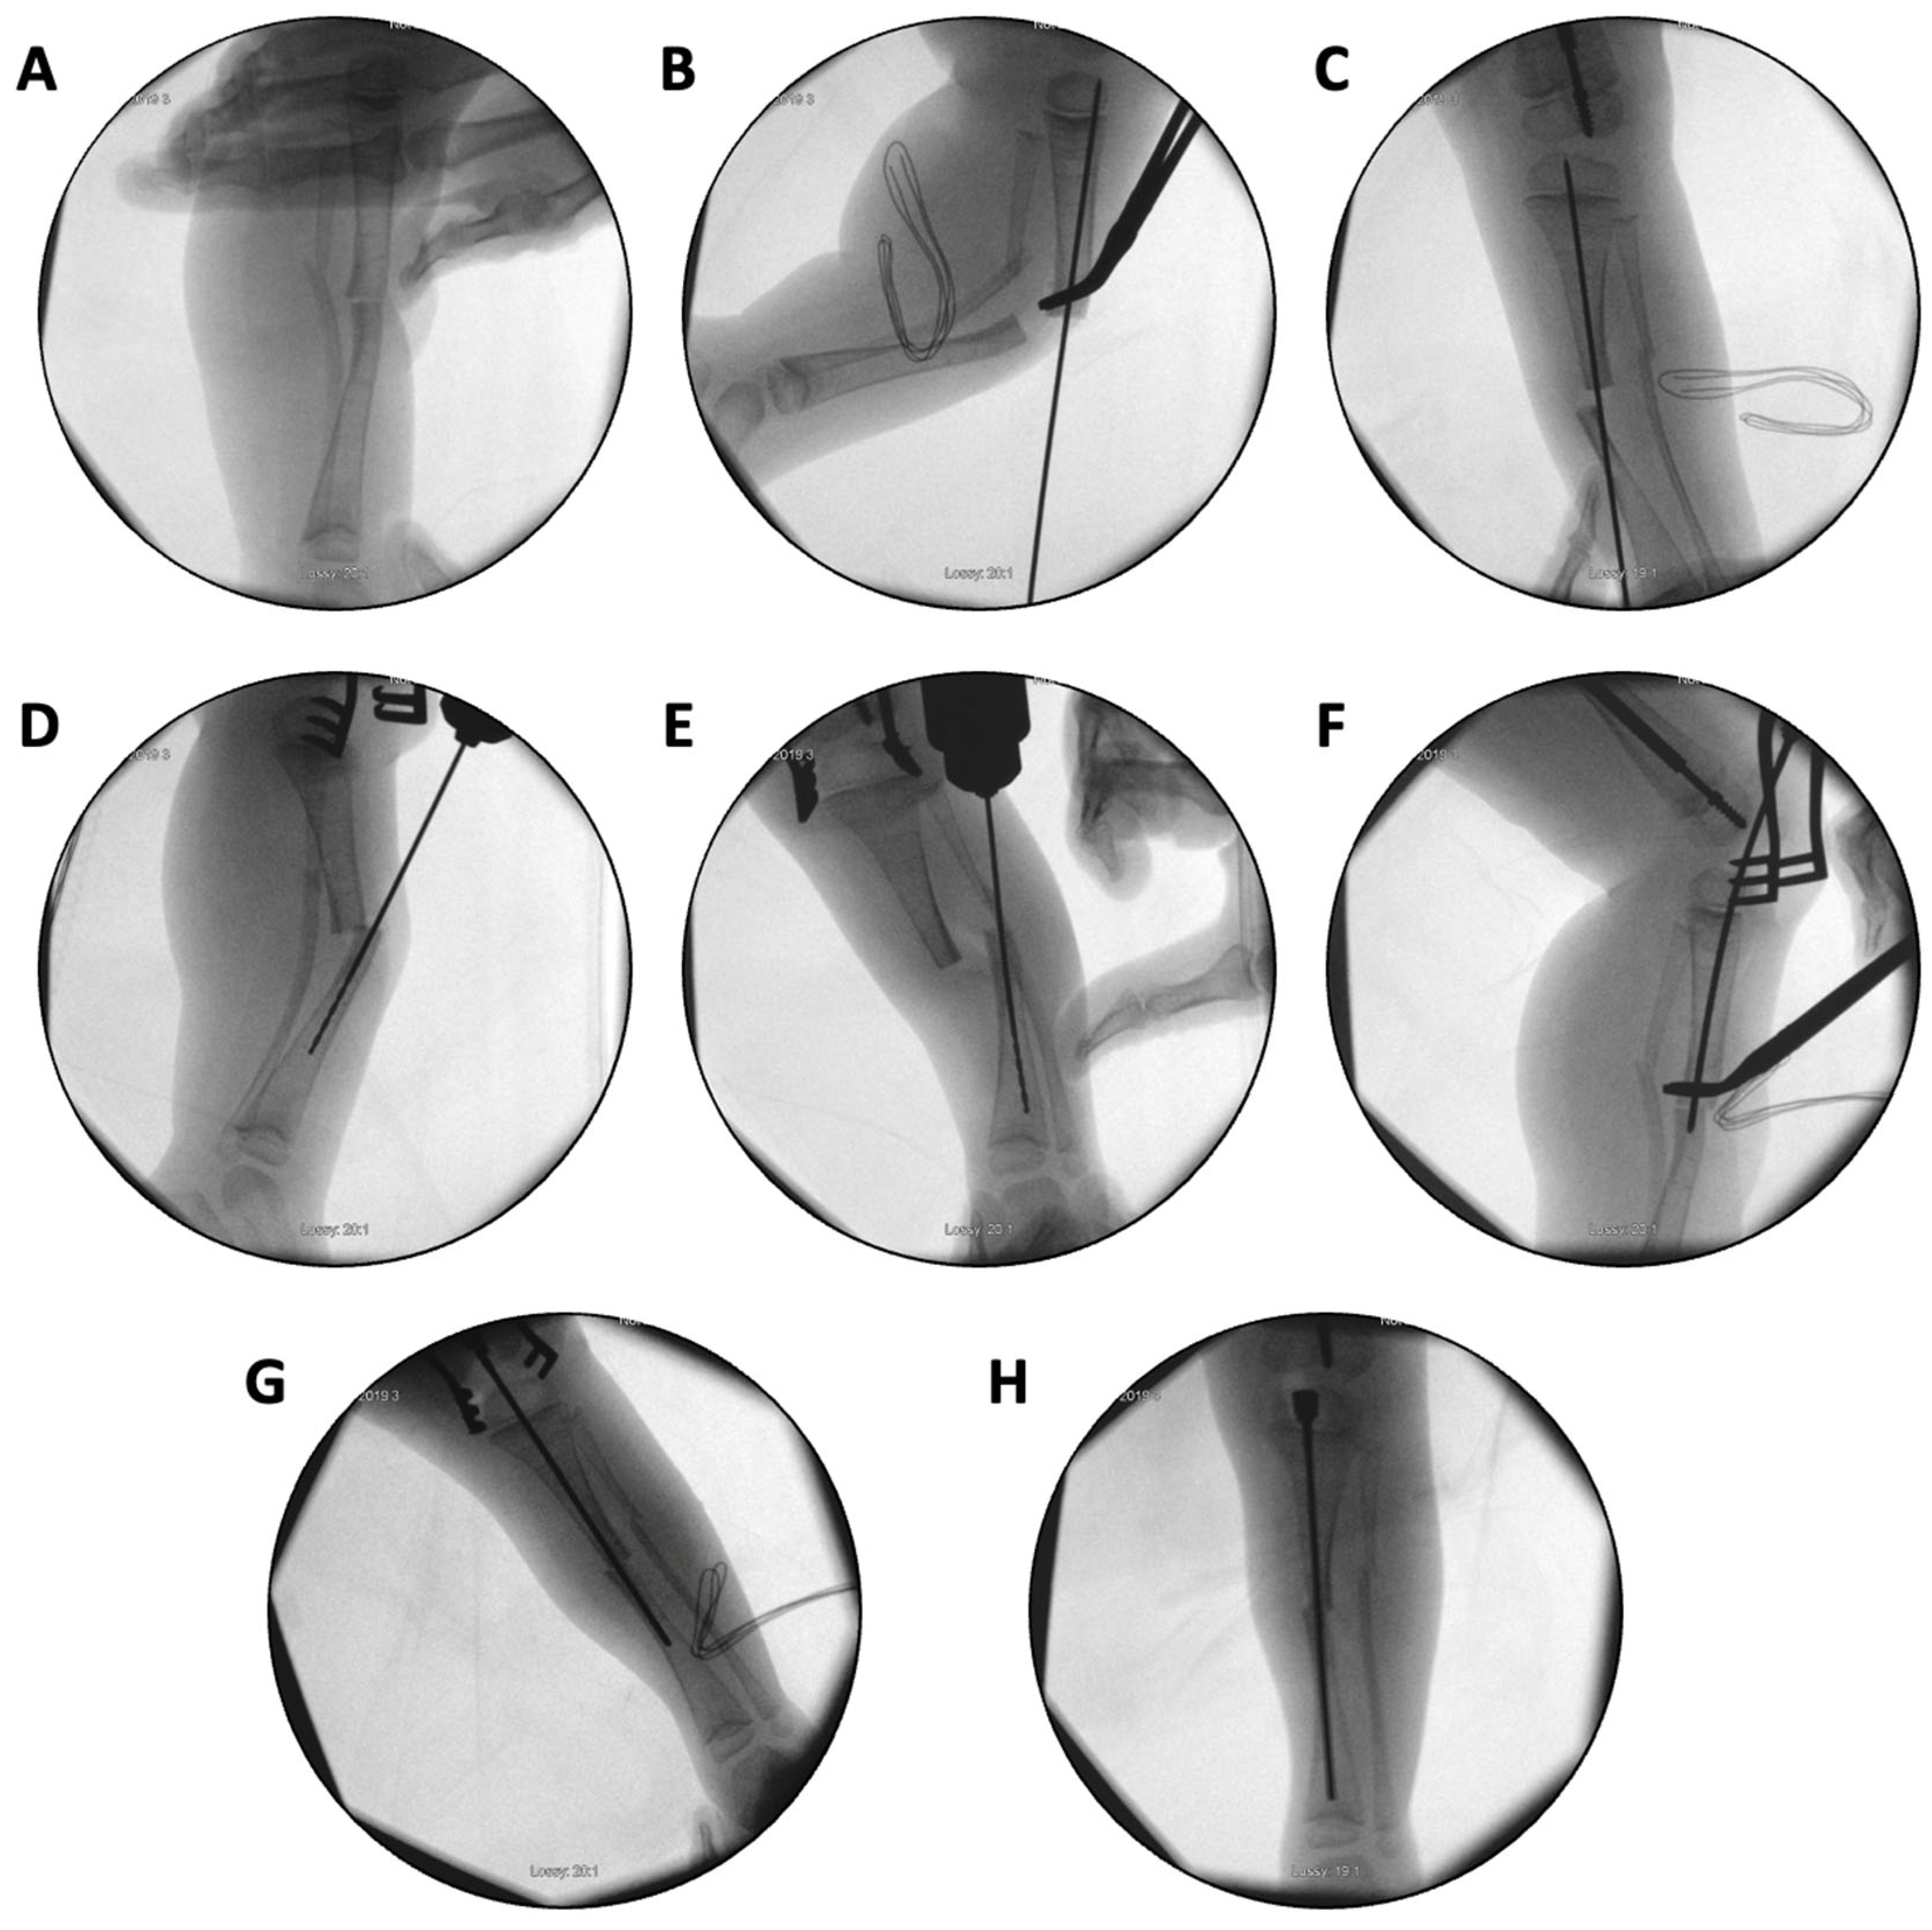

Figure 9.

(A–H): Series of intraoperative fluoroscopy images demonstrating insertion of the SLIM nail. (A) After osteotomy, the fracture is reduced. (B) Lateral view of proximal reaming through the osteotomy site. (C) AP view of proximal reaming through the osteotomy site. (D) Lateral view of distal reaming through the osteotomy site. (E) AP view distal reaming through the osteotomy site. (F) Insertion of the SLIM nail. (G) SLIM nail is gradually advanced past the osteotomy site. (H) AP view of installed SLIM nail, with proximal threading in the epiphysis.